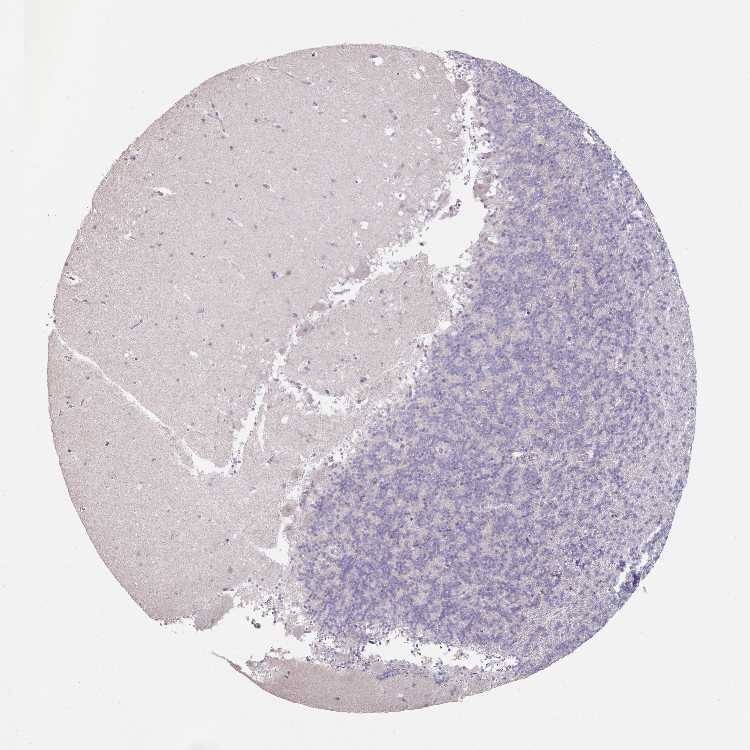

CEREBELLUM - Antibody stainingi

Antibody staining in the annotated cell types in the current human tissue is reported as not detected, low, medium, or high, based on conventional immunohistochemistry profiling in selected tissues. This score is based on the combination of the staining intensity and fraction of stained cells.

Each image is clickable and will lead to virtual microscopy that enables deeper exploration of all samples and also displays staining intensity scores, fraction scores and subcellular localization as well as patient and tissue information for each sample.

Antibody HPA054111

Purkinje cells Low

Cells in granular layer Not detected

Cells in molecular layer Not detected